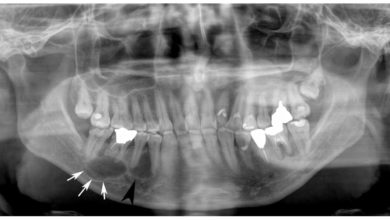

Çene Kistleri

Çene Kistleri Nedir? Kist çene kemiği veya yumuşak doku içinde yer alan içi sıvı veya yarı katı kıvamında madde ihtiva…